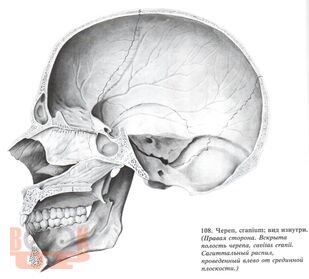

В учебном пособии представлены широкие возможности лучевых методов исследования при патологии области турецкого седла. Большое внимание уделено возможности классической краниографии с учетом новых современных аппаратов, таких как МРТ И КТ.

Методическое учебное пособие иллюстрировано снимками, схемами, дан краткий список литературы. Учебное пособие предназначено для интернов, ординаторов, рентгенологов.